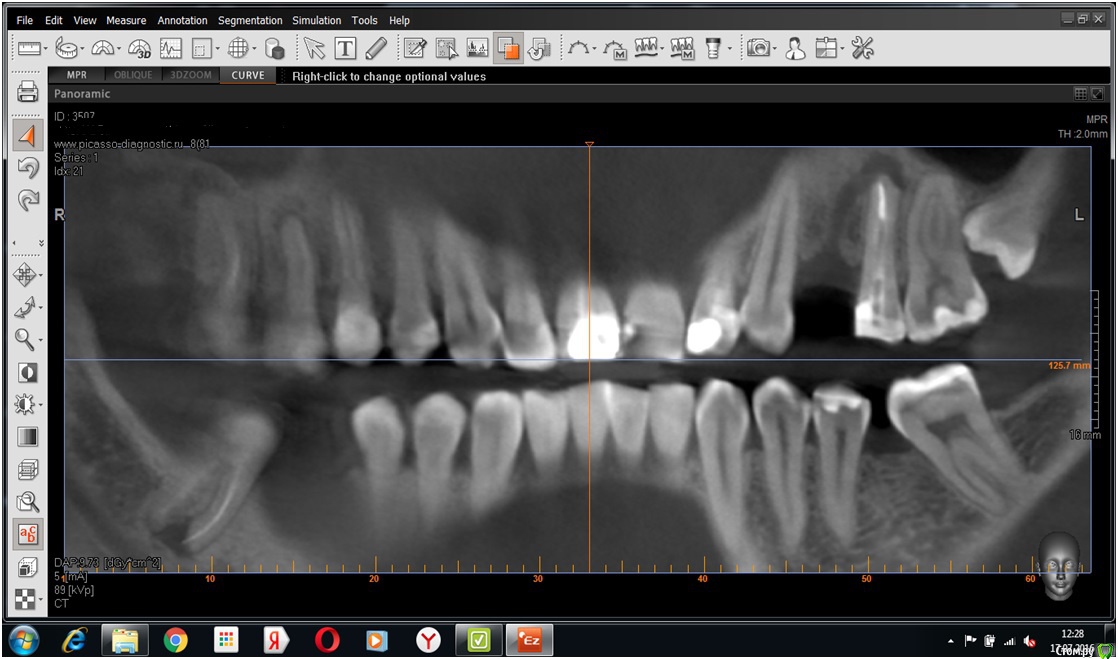

kokobeiko Опубликовано 18 июля, 2016 Поделиться Опубликовано 18 июля, 2016 Пациент обратился с целью имплантации в области отсутствующего 24 зуба, ко мне был направлен с целью перелечивания 25 зуба и дальнейшим покрытием его коронкой. 25 зуб никак не беспокоит, со слов пациента.Вопрос, а есть ли смысл? Смущает меня данная "кротовая нора". И что это? Оставшееся воспаление от ранее удаленного 24 зуба? Ссылка на комментарий

gum Опубликовано 18 июля, 2016 Поделиться Опубликовано 18 июля, 2016 Похоже на канал прорезывания от зачатка зуба, а 24 вообще был или нет? 25 если клинически хороший, я бы перелечил, а канал прорезывания откюретажить и ждать Ссылка на комментарий

Fibez Опубликовано 18 июля, 2016 Поделиться Опубликовано 18 июля, 2016 лечите как обычно. это свищевой ход. 1 Ссылка на комментарий

kokobeiko Опубликовано 18 июля, 2016 Автор Поделиться Опубликовано 18 июля, 2016 лечите как обычно. это свищевой ход.Перелечить 25 и спокойно имплантировать в области 24? Или ждать? Ссылка на комментарий

Fibez Опубликовано 19 июля, 2016 Поделиться Опубликовано 19 июля, 2016 ждать. делать контроль и только потом имплантировать. во-первых: в области имплантации свищу делать уж точно нечегово-вторых: а вдруг не будет эффекта от лечения 25? Потом тогда проще ставить сразу 2.4 и 2.5 Ссылка на комментарий